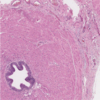

- Diminution spermatogénèse

- Atrophie tubulaire jusqu’à la sclérose

- Appauvrissement en cellules Sertoli

- Cellules Leydig semblent plus proéminentes (car non touchées)

- Épaississement membrane basale des tubules

- Fibrose interstitielle

- +/- GCNIS